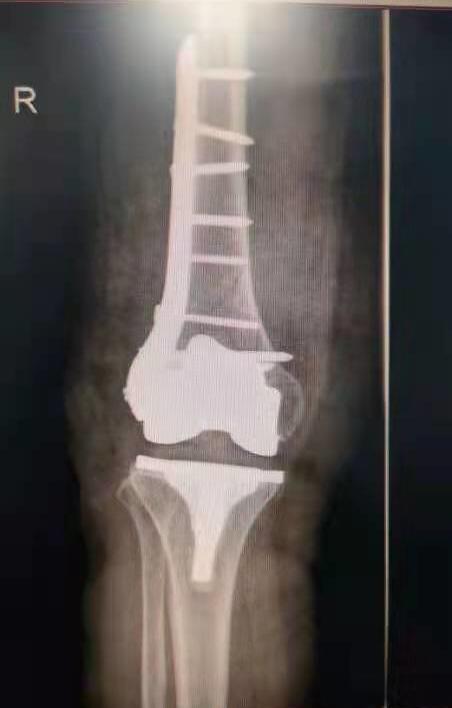

手術(shù)前照片

手術(shù)后照片